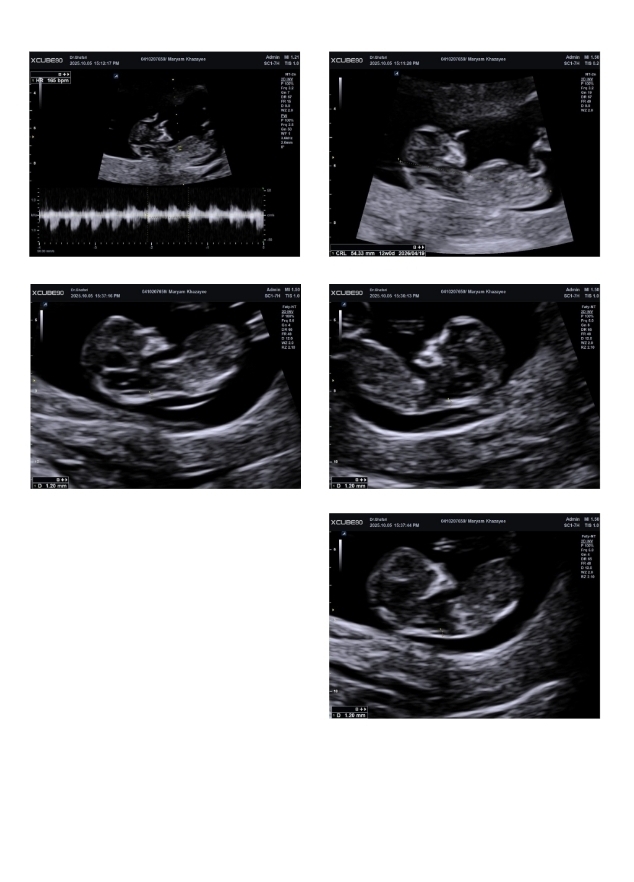

سلام ممنون میشم سونو من رو تفسیر کنید

و اینکه براساس تصویر تصویر به نظرتون دختره یا پسر ؟

ممنون که نظرتون رو گفتید اتفاقا دکتر هم گفت احتمال ۶۰ درصد پسر باشه گفتم نظر دوستانی که اینجا هستن رو هم بپرسم

من ورامینم سونوگرافی دکتر غفاری رفتم

سلام به روی ماهتون مامان جان

برای تعیین جنسیت باید منتظر سونو آنومالی اسکن باشیم

همه چیز عالی است و مشکلی ندارد فقط جهت تفسیر صحیح باید منتظر بخش خون غربالگری باشیم مبارکتان باشد